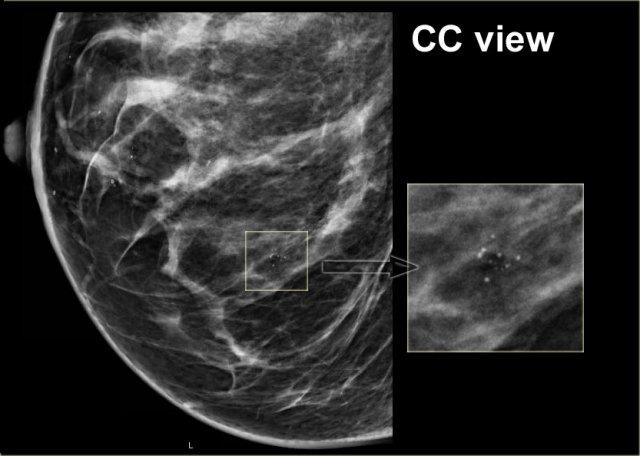

Cụm vôi hóa trên tư thế MLO có cấu hình hoàn toàn giống với cụm trên tư thế CC (hình tiếp theo).

Trên tư thế CC, cấu hình của các vi vôi hóa hoàn toàn giống nhau.

Nếu các vôi hóa này nằm ở trung tâm vú, chúng phải có cấu hình khác nhau vì góc chiếu khác nhau.

Chỉ khi vôi hóa nằm trong da thì cấu hình của chúng mới giữ nguyên.